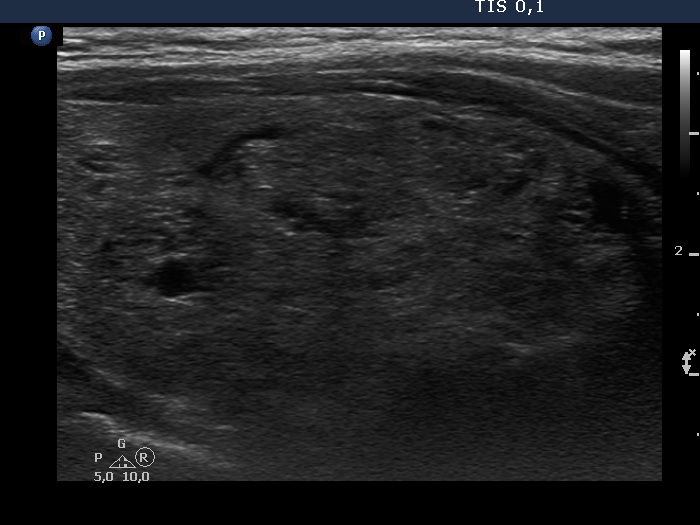

Ultrasonography. The thyroid was greatly enlarged and was composed of numerous nodules. The non-nodular part appeared as echonormal islets within the thyroid. The nodules varied in echogenicity which ranged from moderately hypoechogenic to hyperechogenic. Most nodules had cystic areas, as well. There was no nodule of oncological significance.